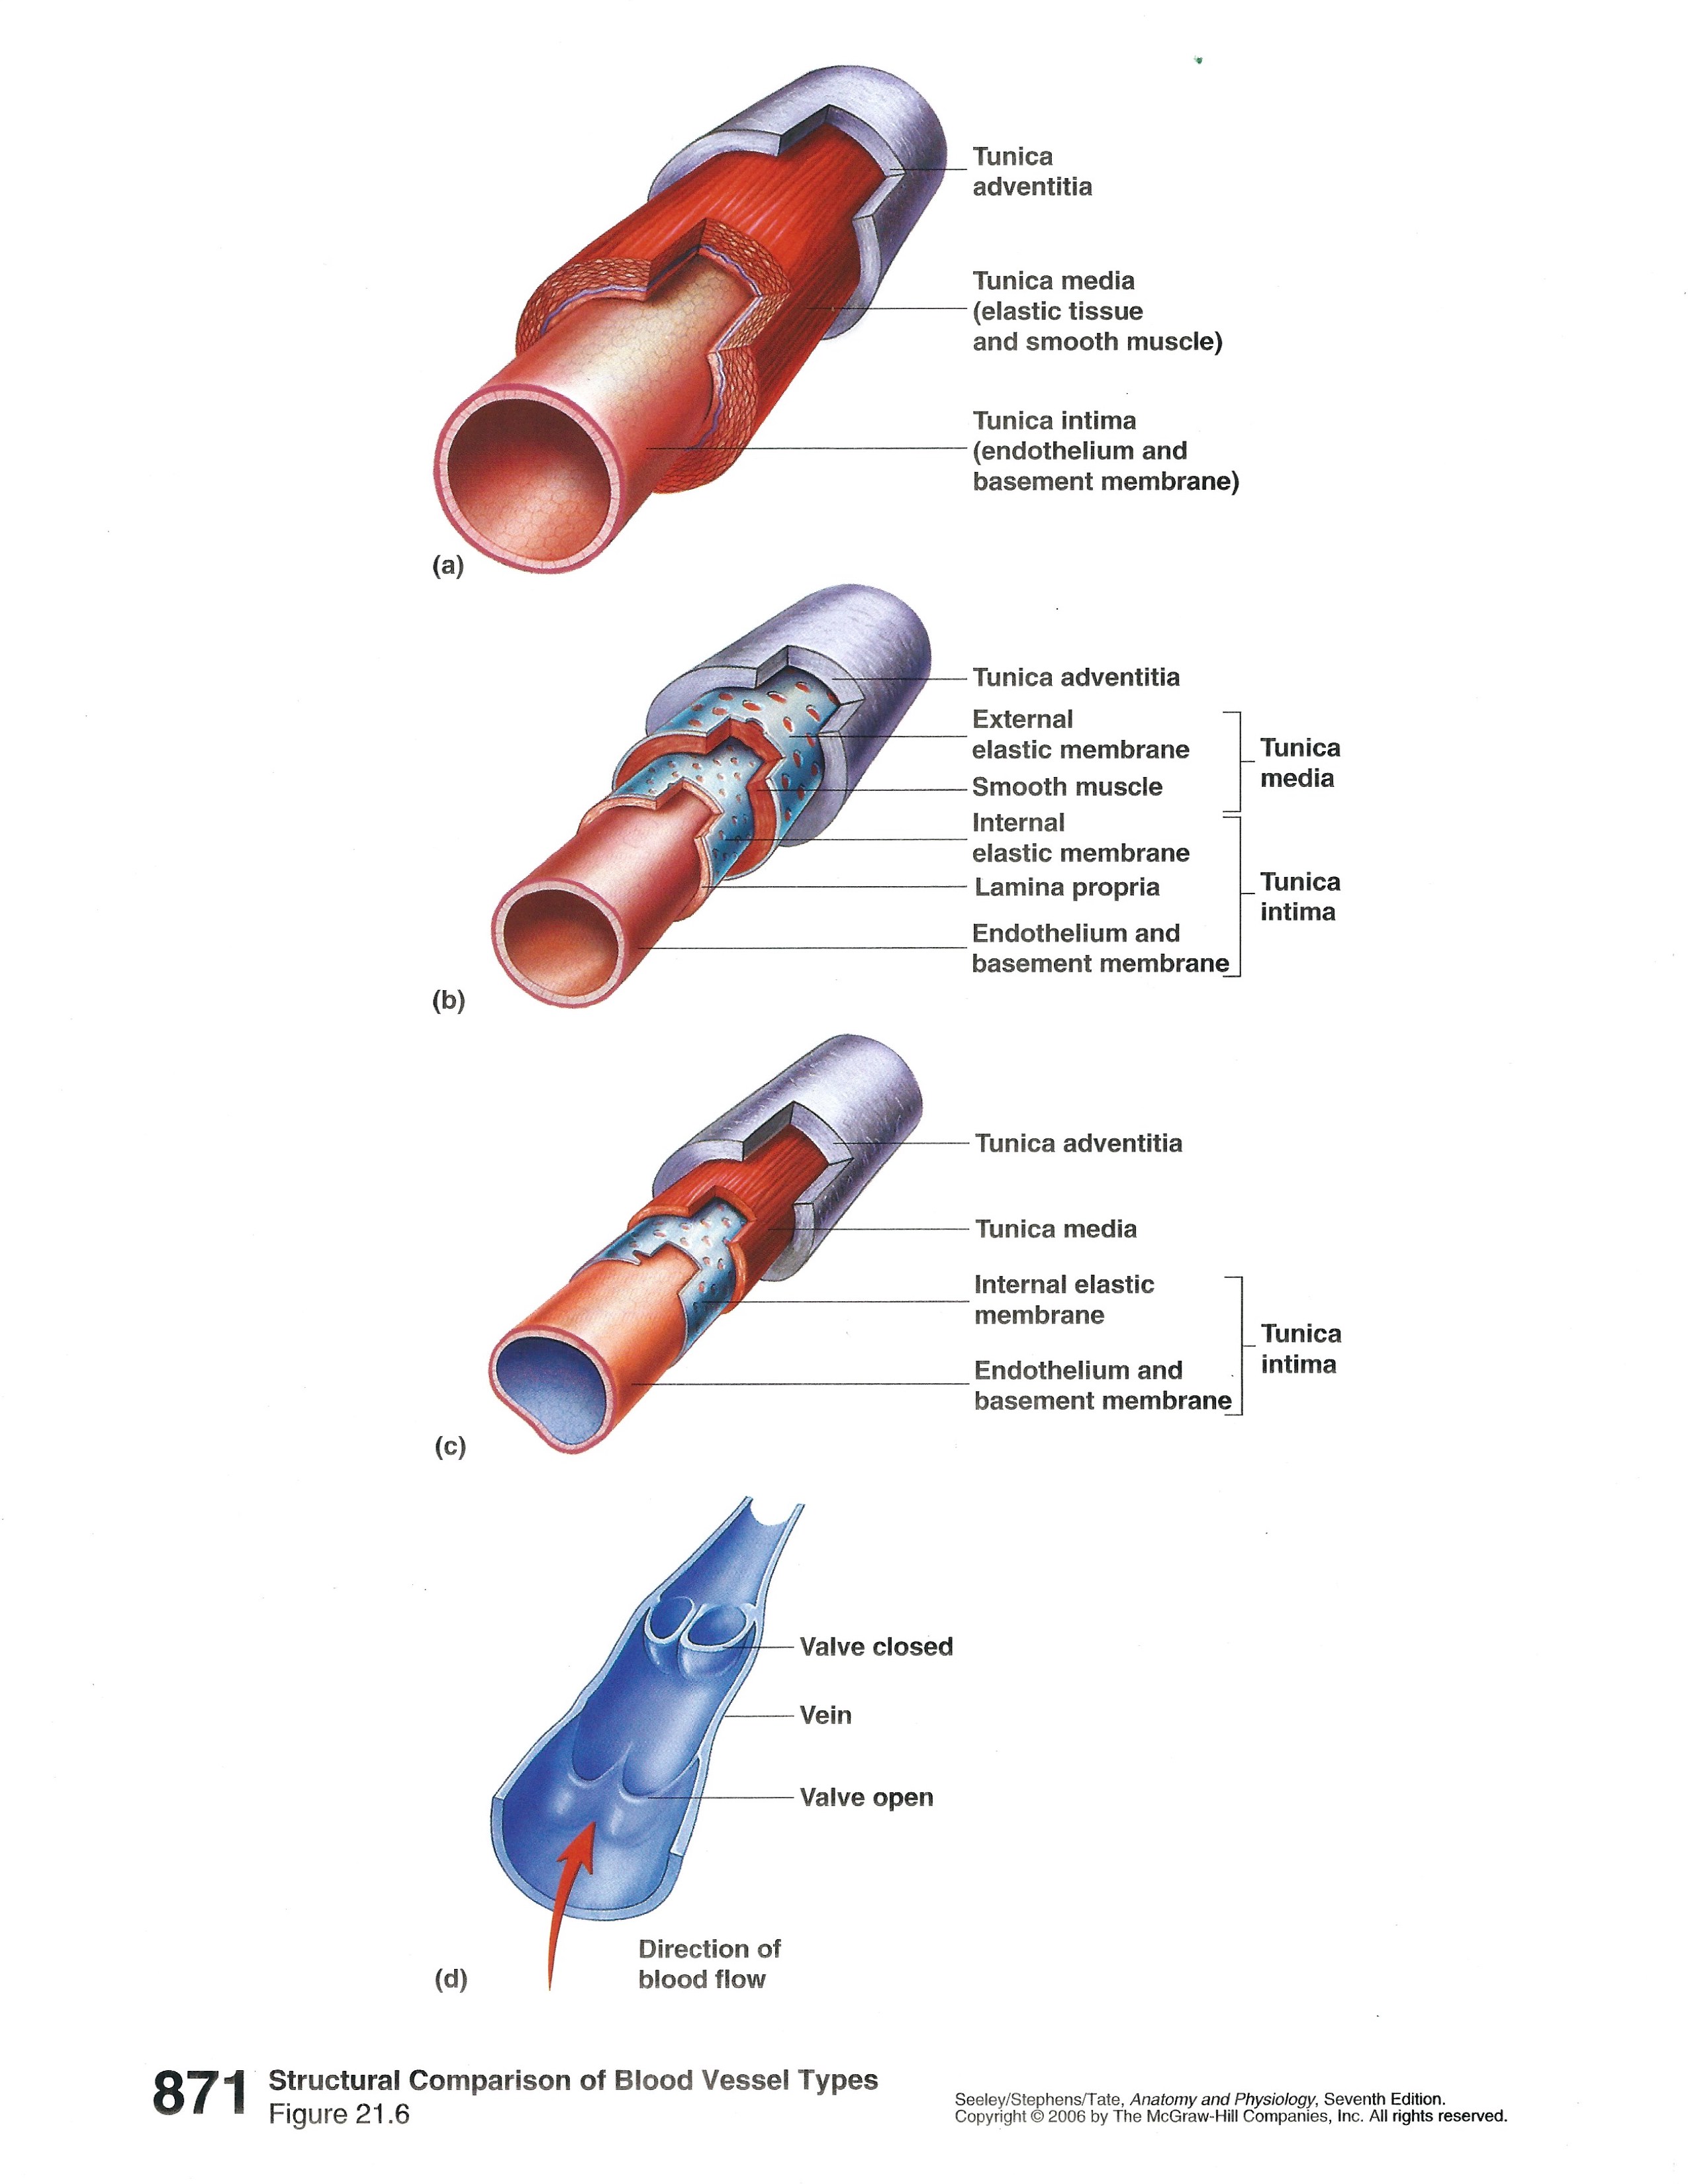

All blood vessels have one or ore layers around them depending on the type of of vessel, artery, arteriole, capillary, venue, or vein.

As you can see, there are considerable differences in the number and thickness of these layers. As usual structure is related to function. Arteries have to withstand the highest pressures as the heart contracts and forces blood into the system. that why you found elastic connective tissue in the walls of the aorta back in histology. Capillaries have a single, simple squamous layer to allow maximum diffusion of materials into or out of the vessel.